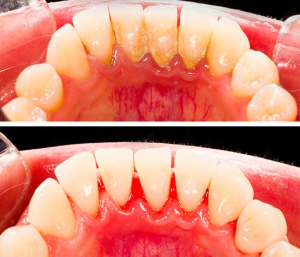

Sebelum & Sesudah Tindakan (Before – After)

Sumber: https://santarosaoralsurgery.com/wp-content/uploads/2021/08/santa-rosa-impaction-bracketing-1.jpeg